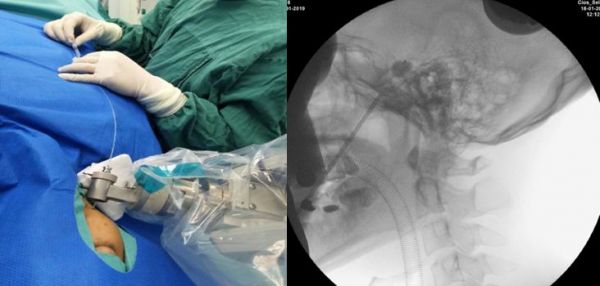

三叉神经痛,俗称“天下第一痛”,是最常见的颅神经疾病之一。2019年初,深圳市第二人民医院功能神经科蔡晓东主任团队成功开展中国首例ROSA机器人辅助经皮穿刺三叉神经半月节微球囊压迫手术(PBC)治疗三叉神经痛。该手术不开颅,机器人精准定位后只需在脸上穿刺一针,一个针眼,术后一个创可贴覆盖即可。手术快速、精确、微创、安全,术后2天患者即出院回家。